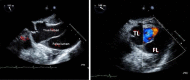

Two Intriguing Cases of Stanford Type A Acute Aortic Dissection

Stanford type A acute aortic dissection (AAD) is a life-threatening illness that presents with chest pain and hemodynamic instability. Prompt and accurate evaluation and management are critical for survival as it is a cardiac surgical emergency. We aim to highlight the physicians about this potentially fatal condition, by reporting two cases of Stanford type A AAD, with atypical presentations that were initially misdiagnosed.

Keywords: acute aortic dissection; aortogram; pericardial effusion; pericardiocentesis; transthoracic echocardiogram.